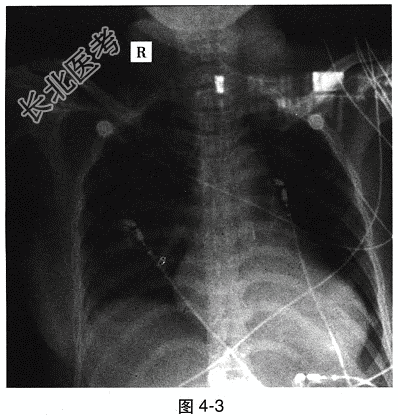

- 多项选择题3.[提示]给予心肌保护治疗,应用“辅酶Q10、环磷腺苷葡胺、磷酸肌酸、利尿剂、新活素”等; 应用“莫西沙星、头孢哌酮钠舒巴坦钠”控制感染。入院5天后,患者突然意识丧失, 心跳、呼吸骤停,心电监护示直线。立即胸外心脏按压、气管插管、机械通气。经抢救, 心律恢复房性异位节律,完全性右束支传导阻滞+左前分支传导阻滞。机械通气情况下, 血压低于90/60mmHg,床旁超声示LA 35mm, LV 52mm,肺动脉收缩压39mmHg, 二尖瓣轻度反流,三尖瓣轻度反流; 心室室壁运动普遍减弱,LVEF 29%。床旁胸部X线片: 双肺纹理增多,心影增大, 心胸比例>50%,心尖向左下延伸, 见图4-3。急性心力衰竭的临床表现是